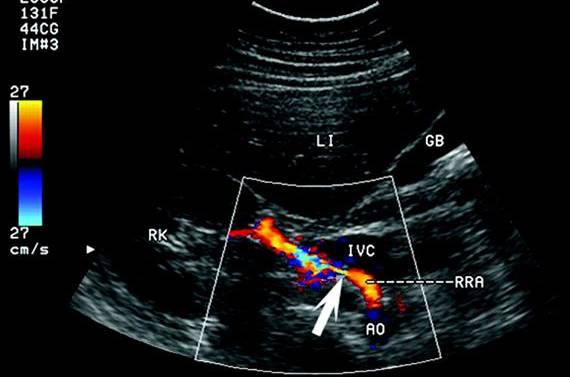

УЗДГ сосудов органов брюшной полости

При обследовании можно обнаружить дефекты строения брюшной аорты и ее ветвей, атеросклеротические изменения, врожденную двойную дугу, стеноз чревного ствола. Показания к проведению: